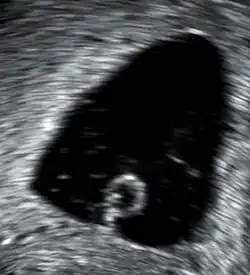

Bradykardia utrzymująca się u płodu w I trymestrze ciąży niemal zawsze poprzedza poronienie[1]. Innymi wskaźnikami nieprawidłowego rozwoju ciąży i zwiększonego ryzyka jej utraty są: nieprawidłowy wzrost pęcherzyka ciążowego, jego nieregularny kształt, hiperechogenność ścian i wczesne małowodzie. Elementem oceny ultrasonograficznej zagrażającego poronienia o niejasnej wartości predykcyjnej jest obecność krwiaka pozakosmówkowego.